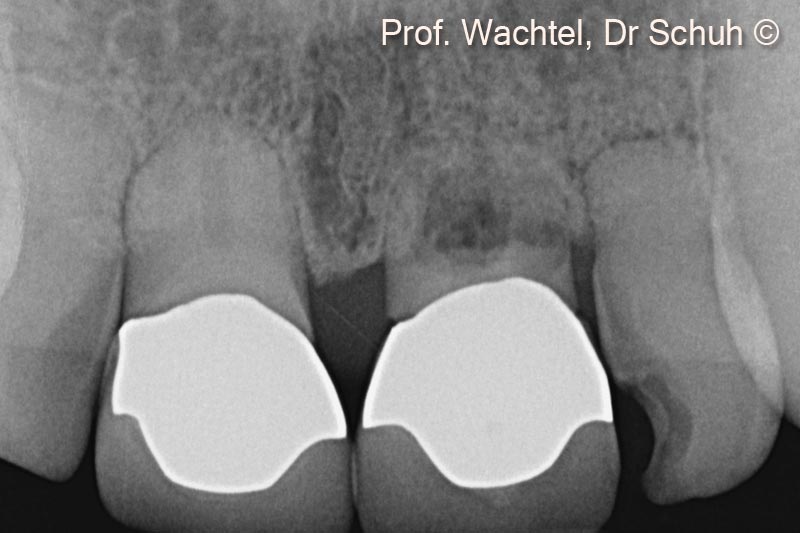

3.  X-ray before treatment displays extended root resorption of all front teeth